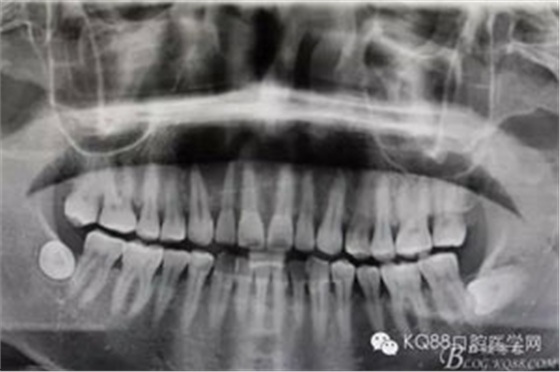

圖1.術(shù)前全景片檢查:11、12、13根尖區(qū)橢圓形陰影,邊界清楚,單囊影。初步診斷:頜骨囊腫